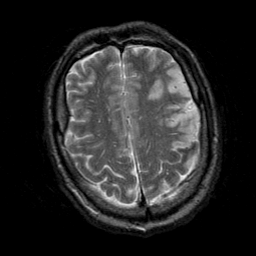

Subacute Stroke, overlay -- Slice #19

[Home][Help][Clinical] Slice 19

Click on sagittal image to select slice. Click on thin tickmark to change timepoint, or thick tickmark for overlay.